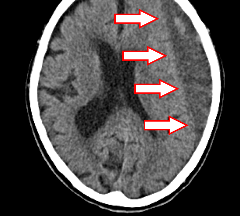

急性硬膜下血腫は脳と頭蓋骨の間に出血するため、脳が血腫により圧迫され、意識障害や麻痺を来す重症の疾患です。

緊急で手術を行なうことで脳の損傷を最小限に抑える外科治療や、脳を保護するための内科的治療を組み合わせて治療を行ないます。

画像では右側頭部に血腫ができています。